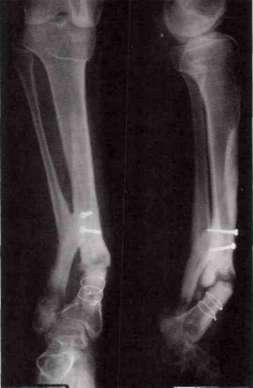

This patient's treatment program proceeded uneventfully, and by June 1969 a good bone union was evident clinically and confirmed by X-ray (Fig. 6). This patient was discharged from the doctor's care.

|

This patient's treatment program proceeded relatively uneventfully. In August 1969, the brace was reported as working well, and no drainage had been experienced since October 1968. Although the fracture had not healed, X-rays revealed some indications of healing (Fig. 7). In March 1970, apparent ankylosis of the ankle joint was noted, and progressive ossification within the fracture area was evident. The patient continues to wear the brace and tolerates it well. He still wears an elastic below-knee stocking, but this is apparently more for insurance than because of actual need.